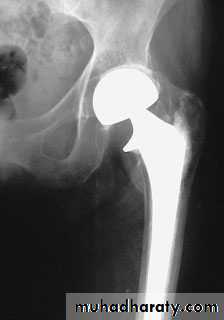

6.Total hip replacement.

Lower limbs